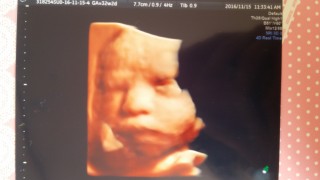

2115gで少し大きめ!笑!今回は真正面から顔を見れたけど仏像!笑!仏像に似てるのにやはり我が子なだけに可愛い…笑。また上の子達に写真見せたらゲラゲラ笑いそぉ…^^;逆子も治ったし良かった♪ママの体重は初診よりプラス2kg♪順調ですね~